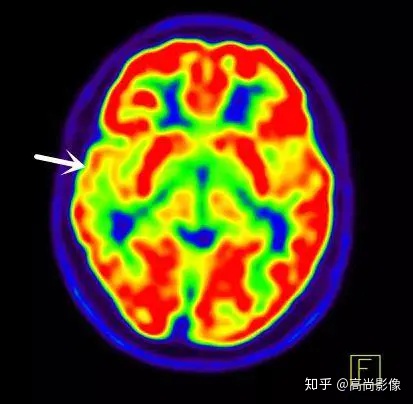

局部18F-FDG代謝顯像主要應(yīng)用于無創(chuàng)定位癲癇病灶。

癲癇是一種發(fā)病率逐年攀升的神經(jīng)系統(tǒng)疾病,其中有相當(dāng)一部分患兒會發(fā)展成難治性癲癇,甚至需要手術(shù)切除。

因此,尋找癲癇病灶就極為關(guān)鍵。雖然頭顱MRI也有針對癲癇的序列掃描,但是MRI提示的結(jié)構(gòu)異常與癲癇發(fā)病之間并不存在必然的關(guān)系,因此對于癲癇發(fā)病預(yù)警及病灶定位來說,單純MRI的檢查是遠(yuǎn)遠(yuǎn)不夠的。

在國際上,18F-FDG代謝顯像是無創(chuàng)定位癲癇病灶的標(biāo)準(zhǔn)。

發(fā)作間期癲癇灶呈代謝減低

發(fā)作期癲癇灶呈代謝增高